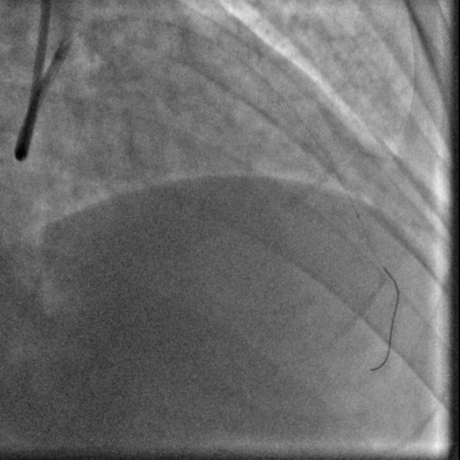

冠脉造影:

经右股动脉(8F),送EBU 3. 5指引导管指引导管至左冠开口。Sionblue导丝至LCX保护,Finecross 130到达LCX远端待命。Sionblue引导Corsair 135cm微导管进入LAD。近段纤维帽坚硬(伴钙化随后IVUS证实)尝试使用Gaia1st进入前次假腔,导丝升级Gaia 3rd谨慎前进入间隔支S1,推送corsair进入S1交换KDLC,Pilot 200导丝平行进入LAD真腔。Corsair交换Sionblue到LAD远端。IVUS证实全程真腔,闭塞段以纤维为主。植入支架完成血运重建。

右足

右头

蜘蛛位

左头